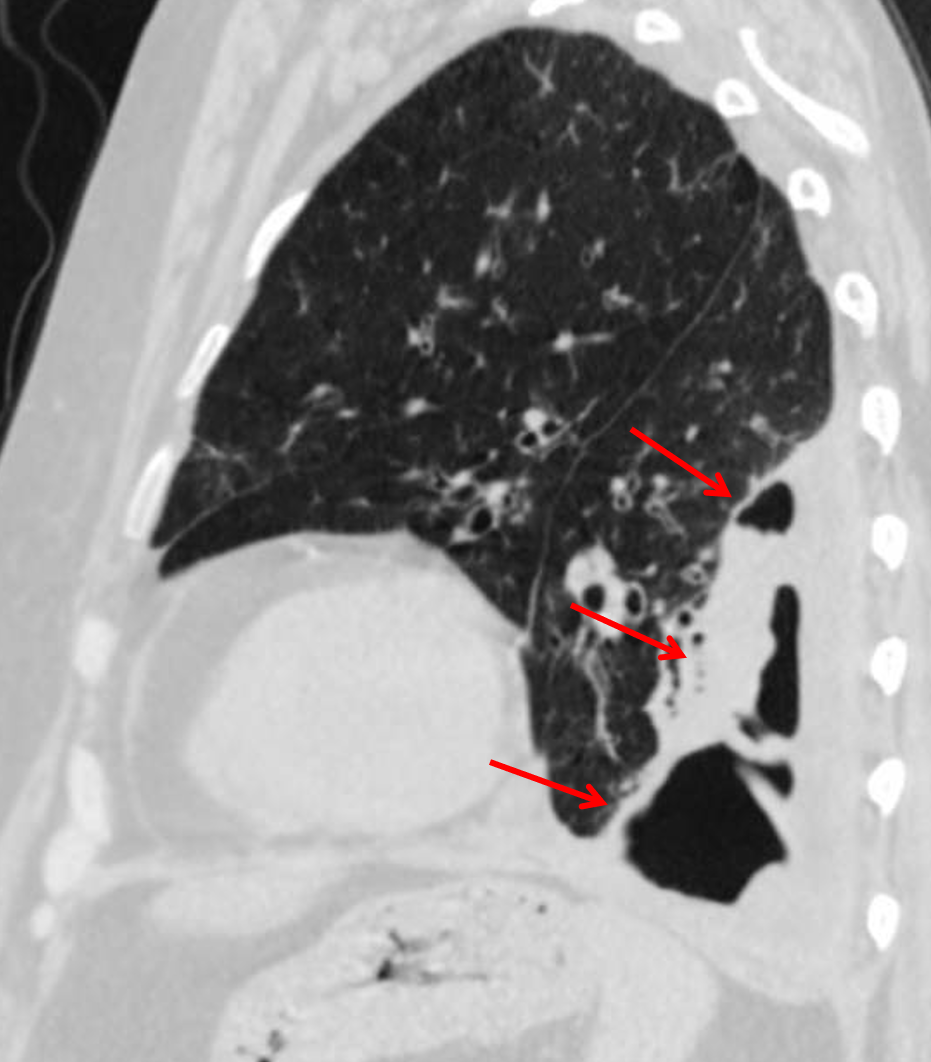

Subsequent CT shows a multiseptated empyema with marked peripheral soft tissue thickening (red arrows).